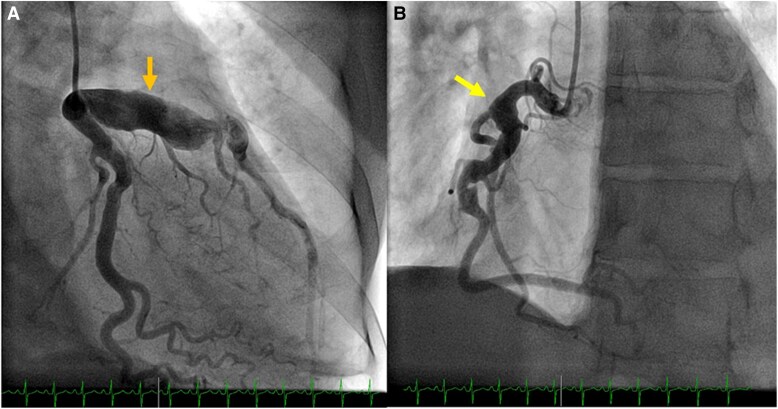

Coronary artery aneurysm (CAA) is a rare, dilated segment of the coronary artery. Phenotypically, it can have different morphologies, patterns, content, and affected vessels, making multimodality invasive and noninvasive imaging play a significant role in its evaluation. In this review article, we discuss in depth the contemporary perspectives in pathophysiology, epidemiology, clinical presentation, multimodality imaging evaluation, treatment strategies (medical, percutaneous and surgical) and outcomes of CAA. CAA is predominantly associated with coronary atherosclerotic diseases and/or autoimmune vasculitis conditions including Kawasaki disease. It can present with various clinical manifestations, from an incidental finding to myocardial infarction and life-threatening complications. While coronary angiography has been the gold standard to detect CAA, noninvasive modalities including coronary computed tomography have increasingly been utilized given its high resolution for anatomical depiction of the vessels and relations to surrounding structures. We suggest a stepwise approach to the assessment and clinical decision-making in the management of CAA. Pharmacological strategies include risk factor control and secondary prevention. For obstructive ischaemic presenting aneurysms, percutaneous is pursued, while larger or multi-vessel obstructive lesions are typically managed with coronary surgery.